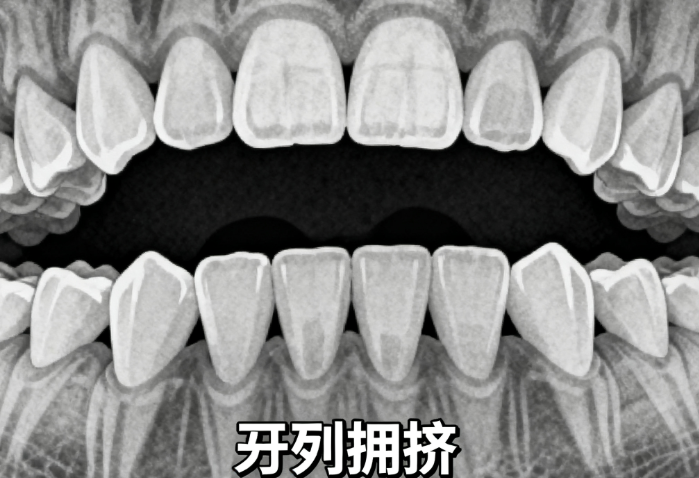

30-40岁成人牙齿矫齿器多少钱?传统钢牙套vs隐形矫正价格大起底!

30到40岁想矫正牙齿,价格从几千到几万都有可能。传统金属托槽价格实惠,适合预算有限的人;陶瓷托槽更美观,适合对外观有要求的患者;隐形矫正则更隐蔽,但价格偏高。不同矫正方式适